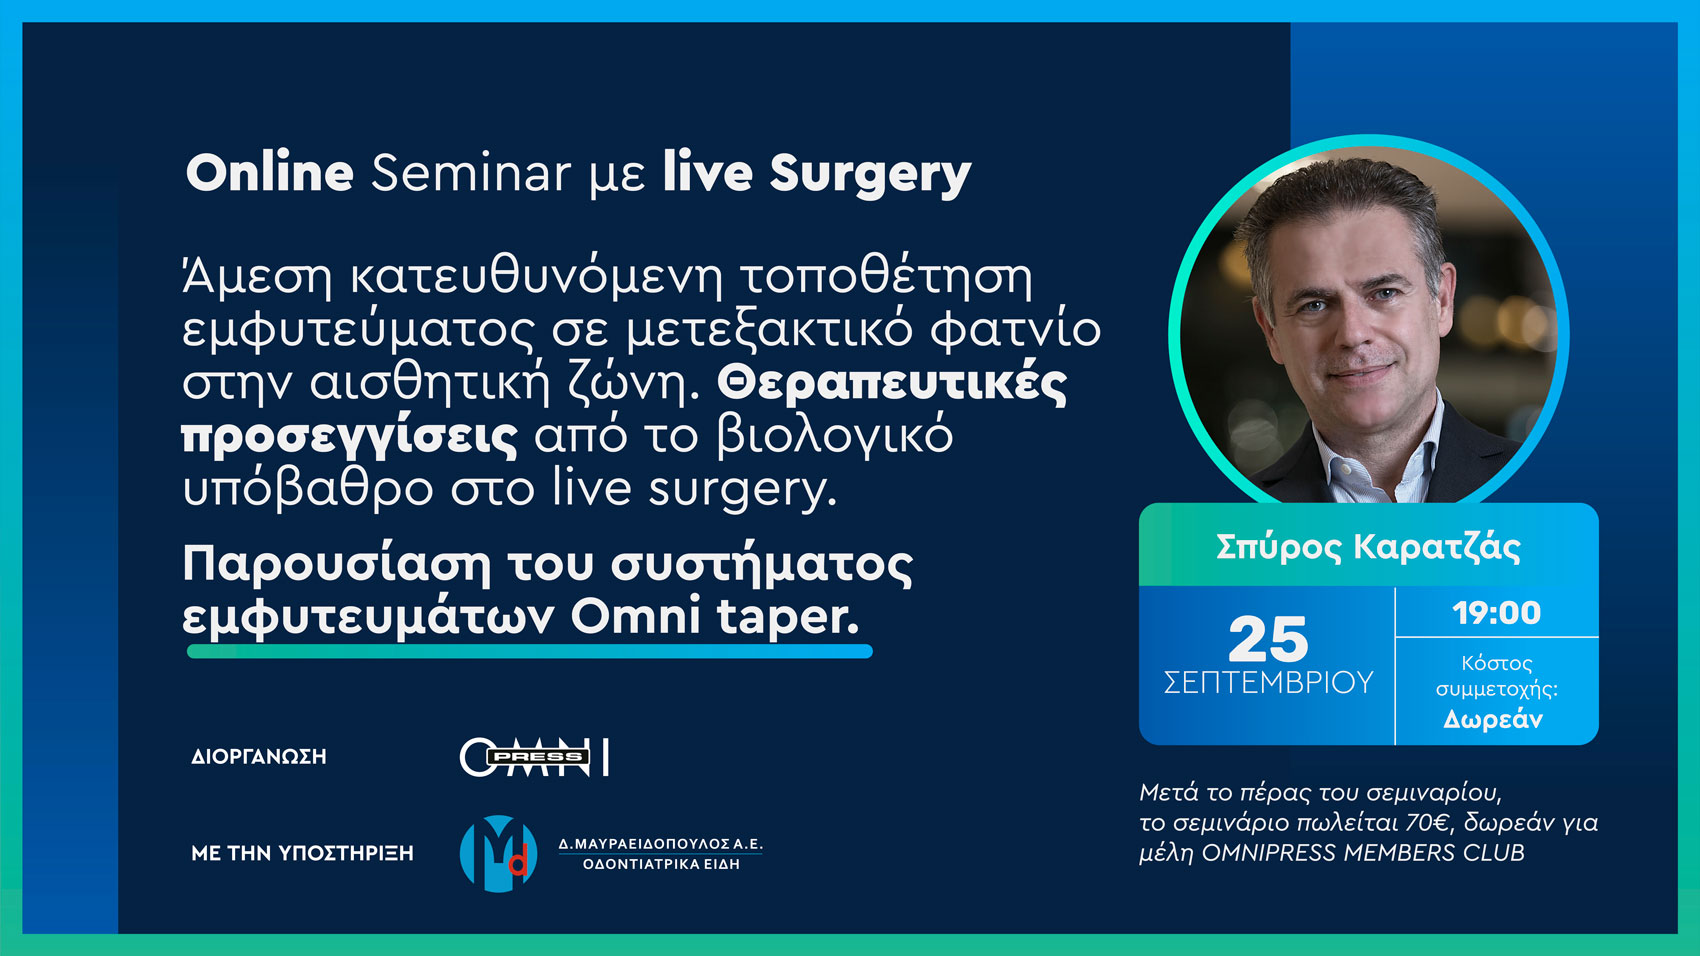

WEBNINAR 25-9-2024 19:00 GREECE

Online Seminar με live Surgery

Διάρκεια: 90’

Άμεση κατευθυνόμενη τοποθέτηση εμφυτεύματος σε μετεξακτικό φατνίο στην αισθητική ζώνη. Θεραπευτικές προσεγγίσεις από το βιολογικό υπόβαθρο στο live surgery.

Παρουσίαση του συστήματος εμφυτευμάτων Omni taper.

Εκπαιδευτής:

Σπύρος Καρατζάς

Με την υποστήριξη:

Μαυραειδόπουλος Δ.

Διοργάνωση

OMNIPRESS

Κόστος Συμμετοχής

Κόστος Προβολής: 70€

Για τα μέλη OMNIPRESS MEMBERS CLUB

Premium & Ultimate: Δωρεάν